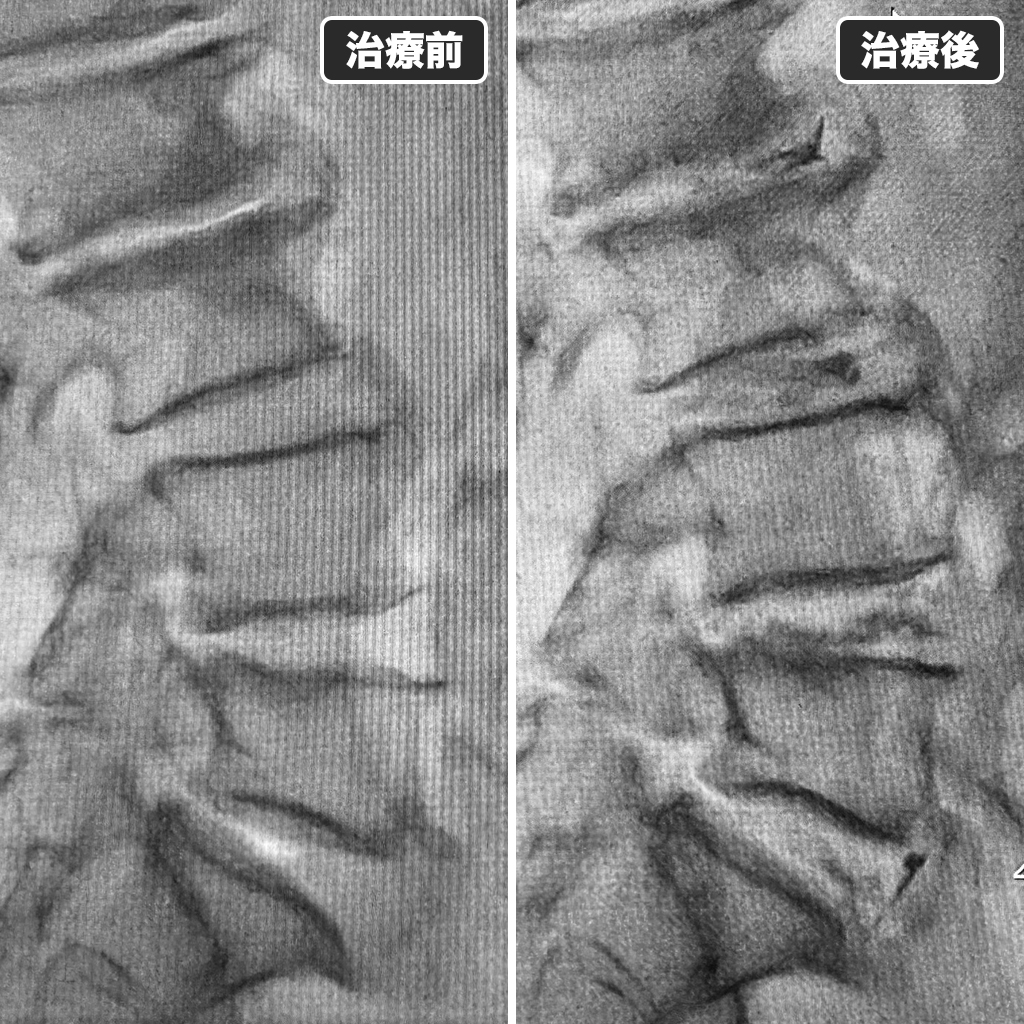

治療前後のレントゲン写真

治療前後のレントゲン写真です。左側が治療前で右側が治療後になります。患者様のご希望もあり、鎮静剤の使用量を少なめに致しましたが、治療中の記憶はほとんどなかったようです。